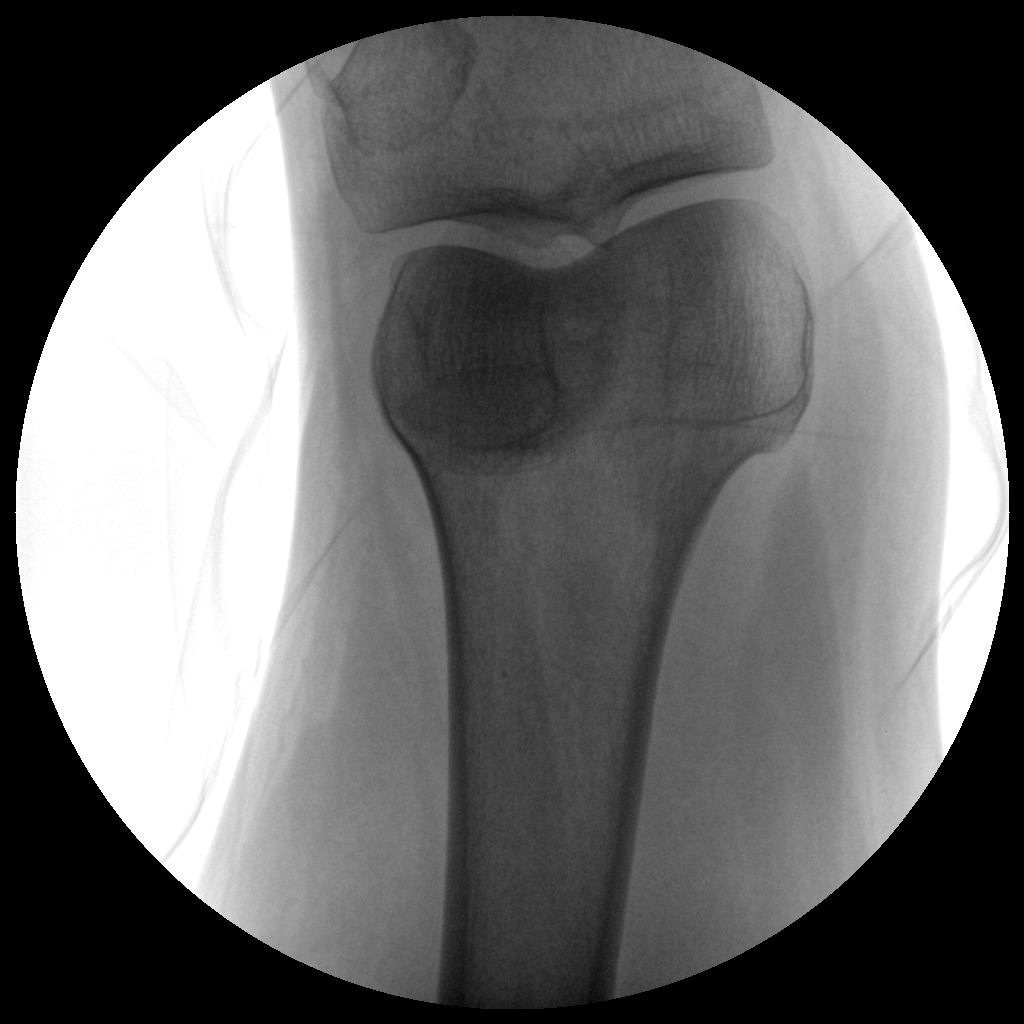

PLX112C 系列高频移动式手术X射线机

手术导航定位系统

●经典图文工作站,搭配双监双控,操作更自如●全数字化百万像素影像系统,图像清晰●独特的电动辅助支撑臂设计, 临床操作轻松自如●具备多种工作模式,满足更多临床需求●人体图形化触摸屏设计,操作方便快捷